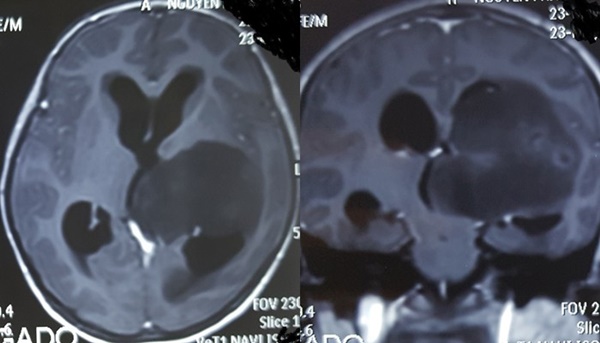

Hình ảnh khối u lớn trong não bệnh nhi (Ảnh: Vietnamnet).